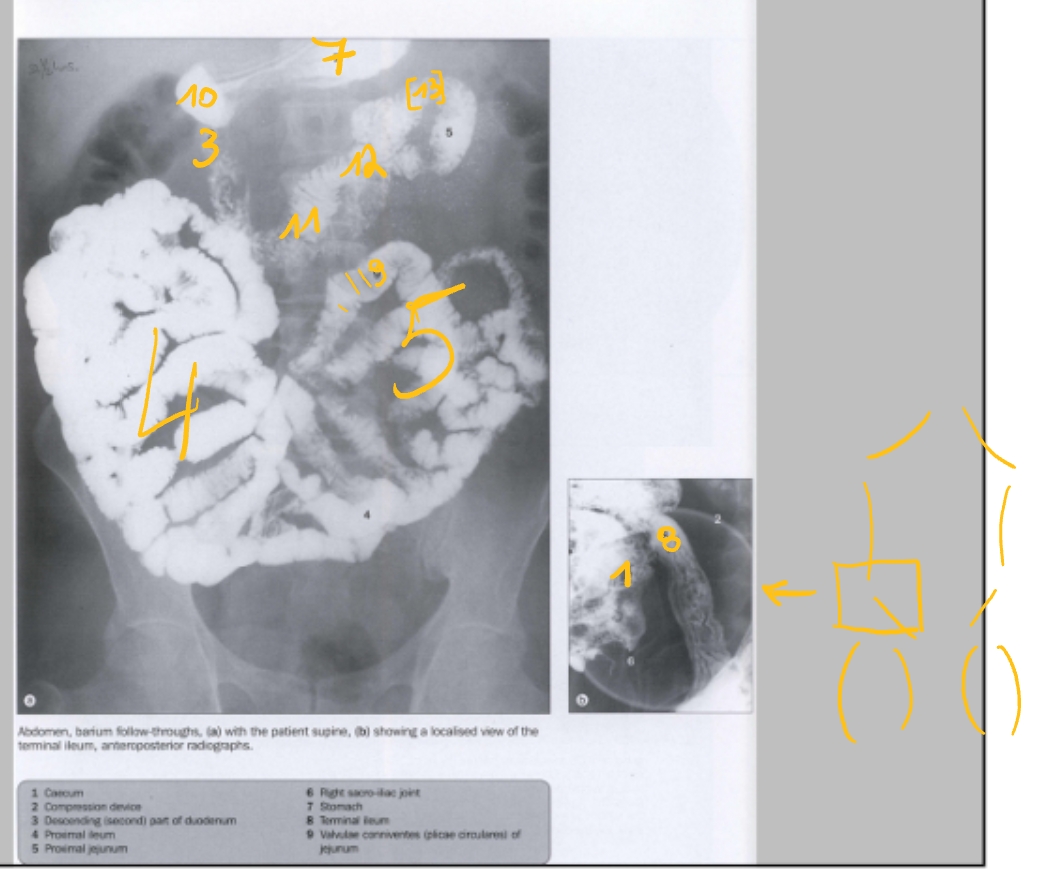

(transit-onderzoek)

maag

duodenum, pars descendens

jejunum

ileum

laatste ileale lis

caecum

colon ascendens

→ A: haustra’s (lopen niet door)

colon transversum

colon descendens

colon sigmoideum

plicae circulares

bulbus duodeni

pars transversa duodeni

pars ascendens duodeni

hoek van Treitz

(= overgang van pars ascendens duodeni naar jejunum)

(dubbelcontrast → bariumsulfaat + lucht)